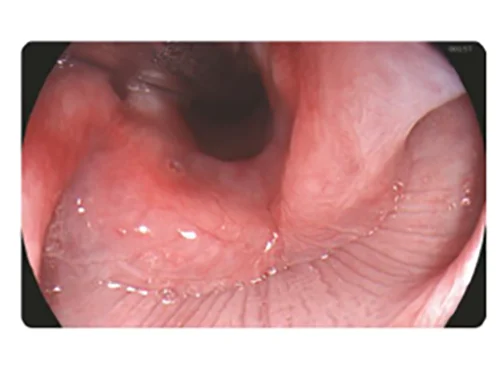

Белый свет

DSI

Белый свет

PSI